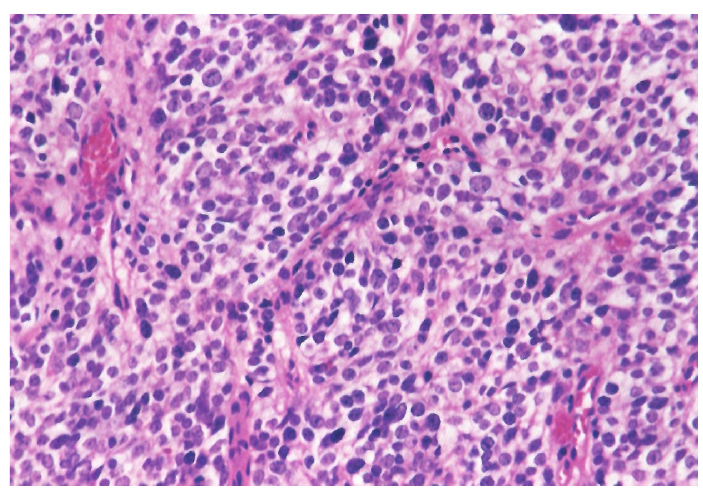

Опухоль с одинаковой частотой локализовалась в правой и левой половинах носа. Но из-за близости соседних анатомических структур и особенностей местнодеструирующего роста опухоли, у двух пациентов первичный очаг изначально диагностировали интракраниально (22,2 %), у двух – в верхнечелюстной пазухе (22,2 %), у одного – в носоглотке (11,1 %) и у двух пациентов (22,2 %) из-за степени распространенности процесса было невозможно анатомически точно определить область первичного возникновения опухоли. В таких ситуациях единственным способом верификации морфологической принадлежности злокачественного процесса является гистологическое исследование (рис. 1).

Эстезионейробластома по своей гистологической структуре напоминает лимфосаркому или симпатобластому и представлена комплексами гиперхромных клеток со структурами типа ложных розеток и скудным нейрофибриллярным матриксом, выраженным полиморфизмом [3, 6].

Рис. 1. Ольфакторная нейрогенная опухоль полости носа (эстезионейробластома, клеточный полиморфизм) ×320 (окраска Г-Э)